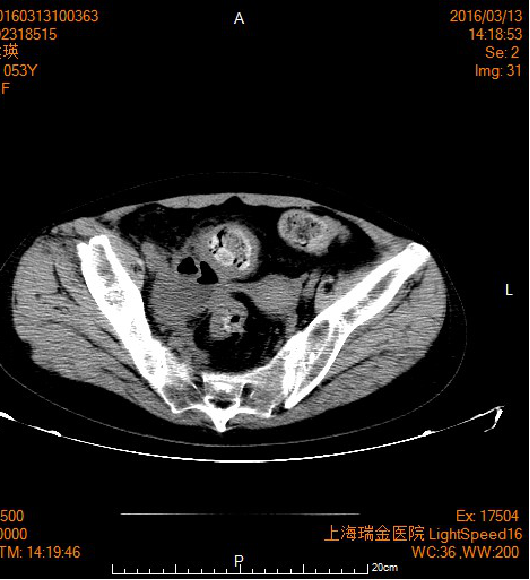

2016.3月患者无明显诱因出现腹痛,以下腹为著,伴发热,体温最高达39.5℃,就诊于我院急诊,予以输液保守治疗,患者未缓解。症状反复发作,3.14日因腹痛症状加重,伴腹胀,急查上腹部CT平扫:腹腔内游离气体,考虑消化道穿孔,腹腔积液,盆腔CT平扫:右侧盆腔液性包块伴周围少量渗出影(积血?),较前片明显增多;乙状结肠管壁增厚,边缘游离气体影,拟消化道穿孔。急诊拟“消化道穿孔”收治创伤外科。

2016.3.18予行直肠癌根治术(hartmann)(远端关闭,近端造口)+腹腔粘连松解术。探查见脓性腹水约500ml,肿块位于直肠上段,约8*7cm大小,已穿破浆膜层,前侵至子宫,右侵至右侧腹壁,后侵至后腹膜,部分结肠与小肠、腹壁、肝脏间相互粘连。